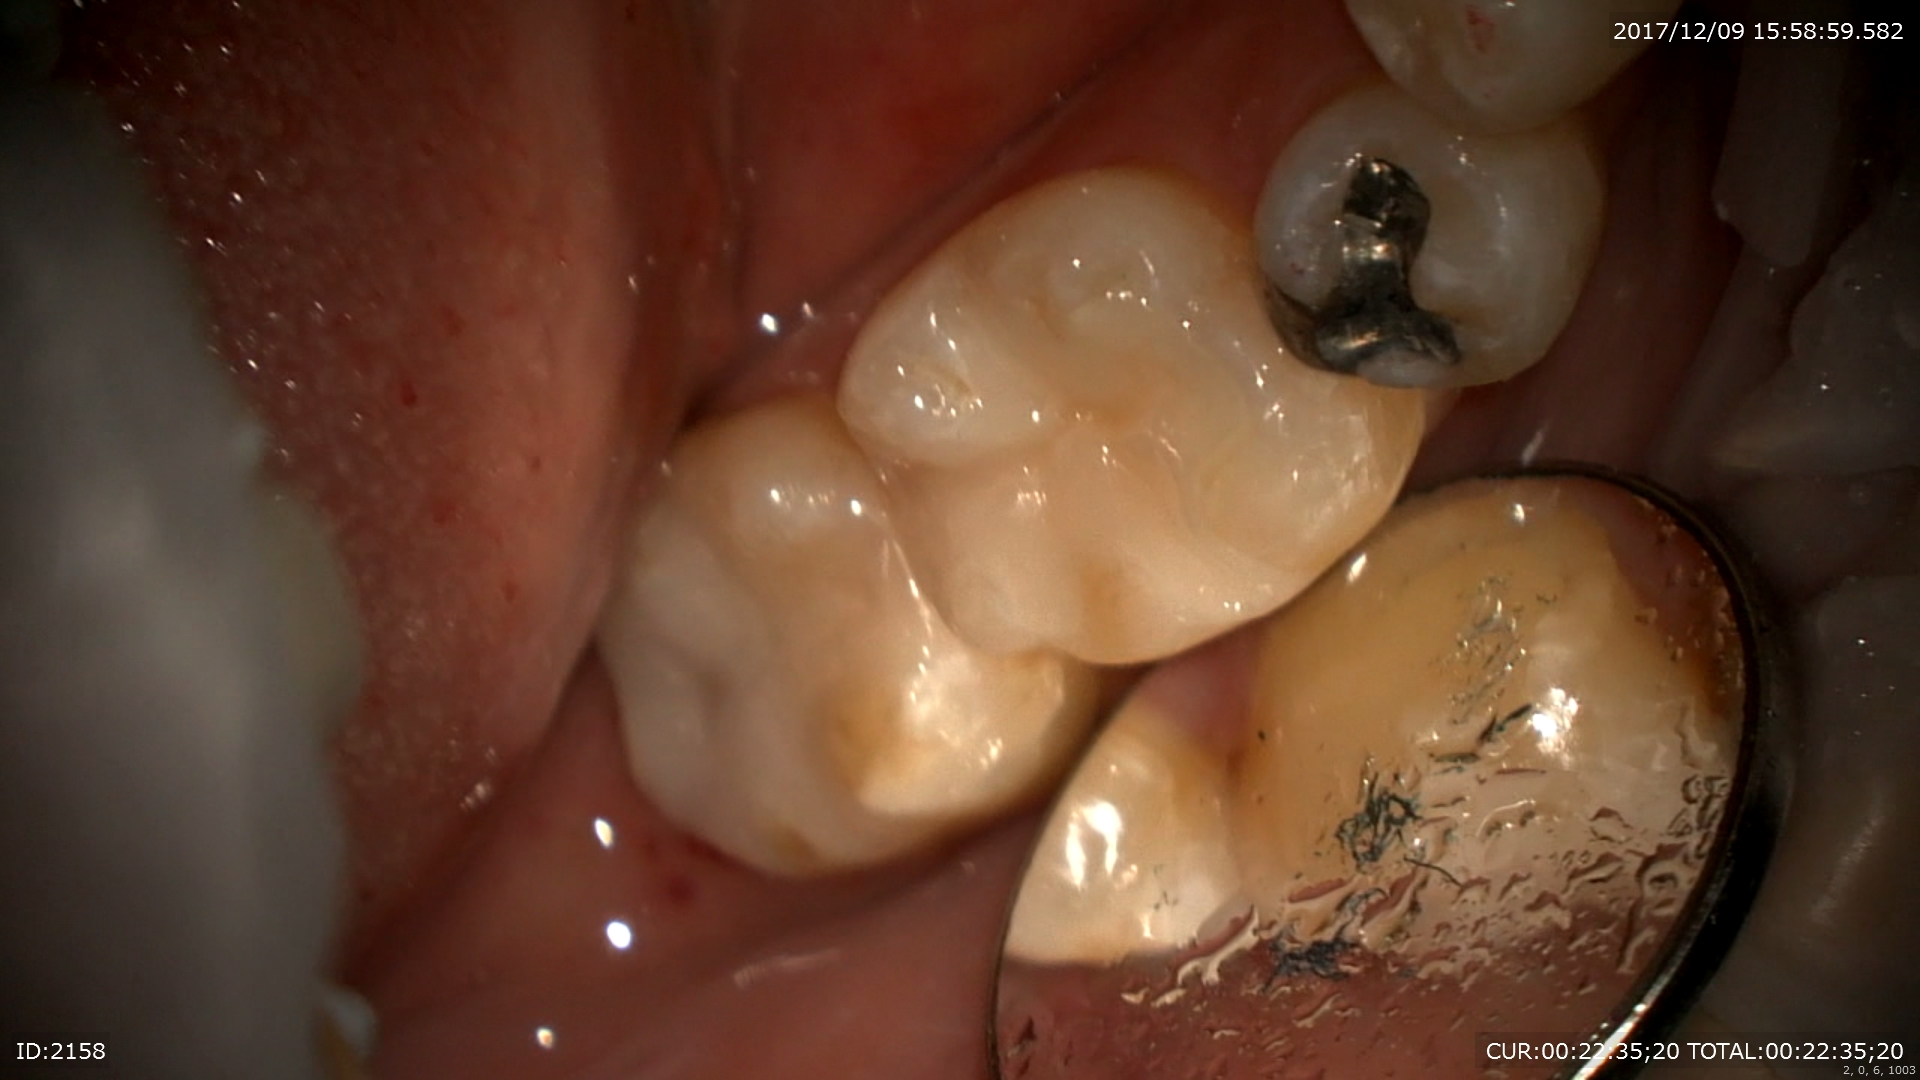

最後はセラミック治療

術前右。術後左。金属を使用しない治療は体に良いと証明されています。

かみ合わせも確認。

患者さまも金属がとれて喜んでいました。僕も幸せ!